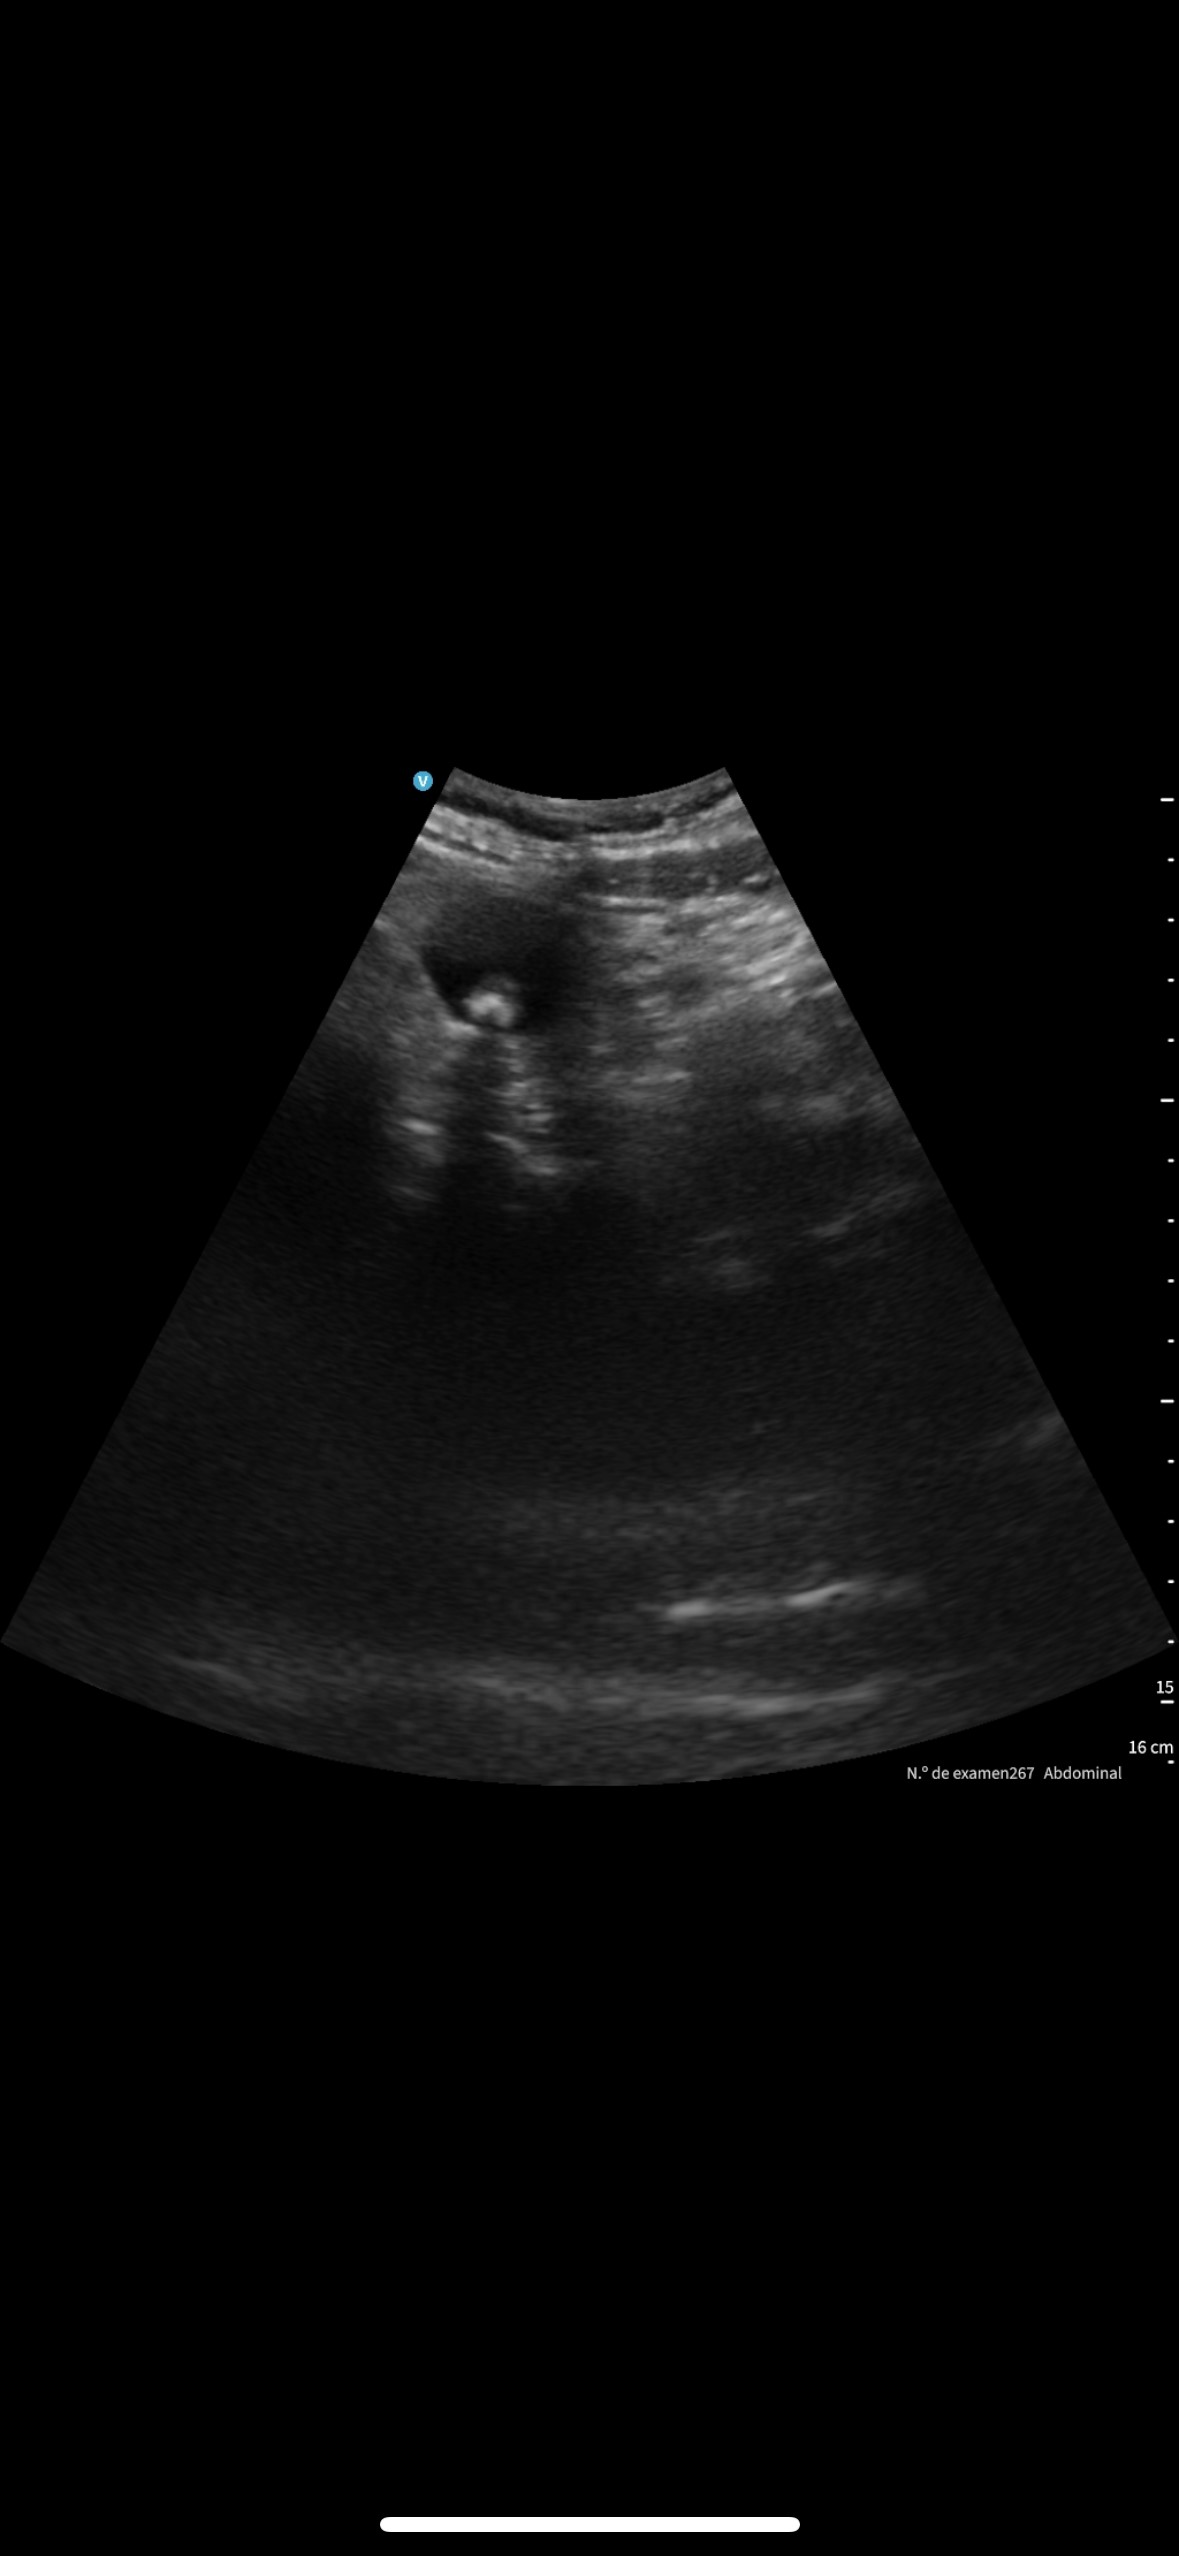

Se le cita en ayunas y realizamos una ecografía abdominal.

En la exploración abdominal se objetiva un cardias laxo de 2,19 cm, y la vesícula biliar distendida con colelitiasis múltiple.